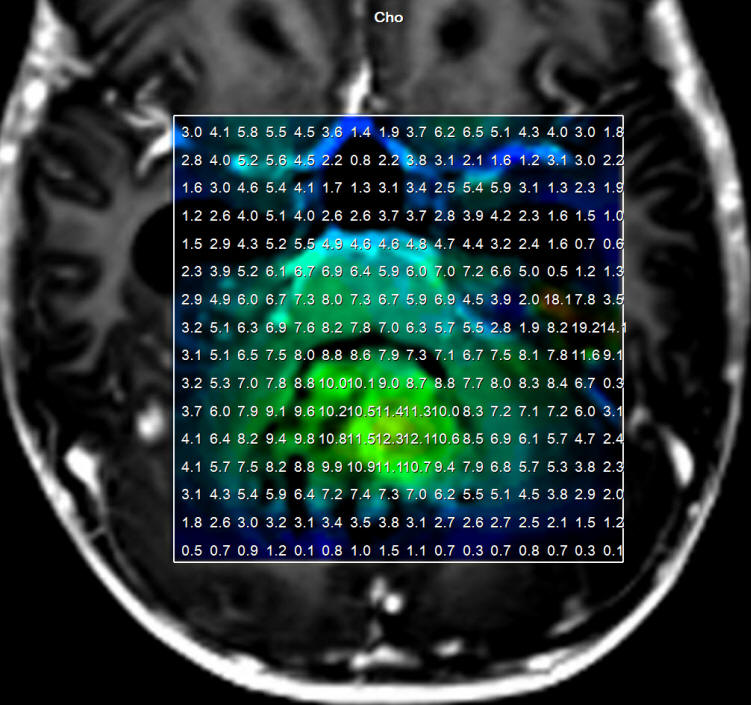

Fig-1: Choline distribution showing a small nidus of possible malignant character befor attacking the lesion.

Fig-5: Choline elevation confirming still persisting active sites intermingled with the hematoma in the right side.

Fig-32: Choline distribution in the medulloblastoma.